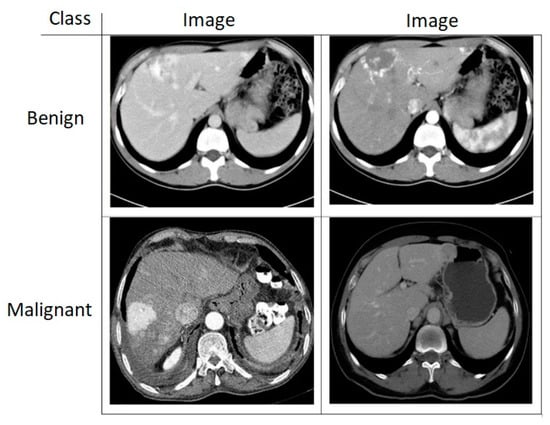

4.1. Dataset